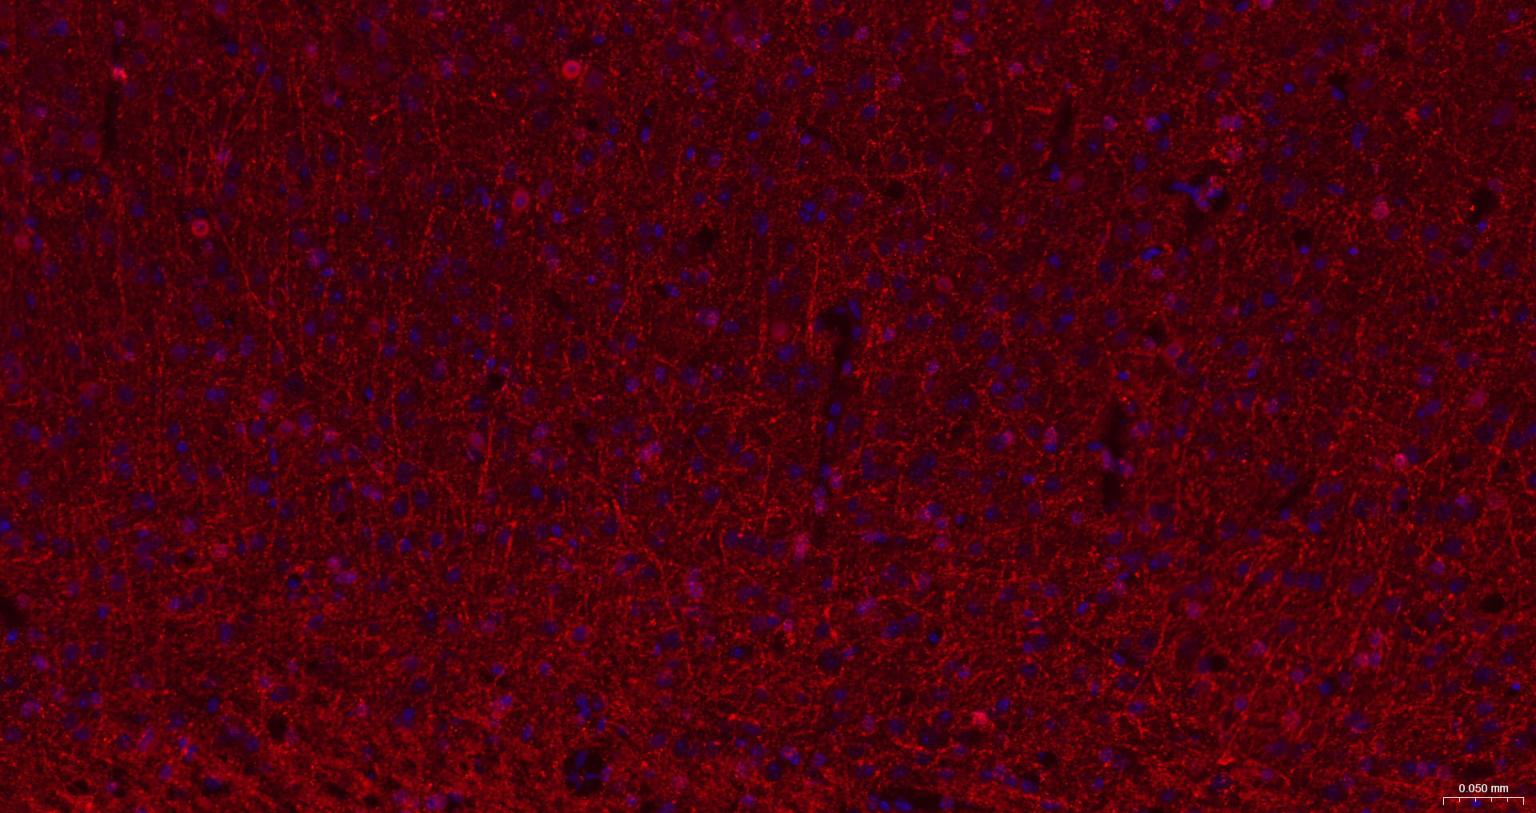

Paraformaldehyde-fixed, paraffin embedded Mouse Cerebrum; Antigen retrieval by boiling in sodium citrate buffer (pH6.0) for 15 min; The section was incubated with CNPase Monoclonal Antibody, Unconjugated (bsm-61411R) at 1:200 overnight at 4°C. Followed by conjugated Goat Anti-Rabbit IgG antibody (Red, bs-0295G-BF594), DAPI (blue, C02-04002) was used to stain the cell nuclei.